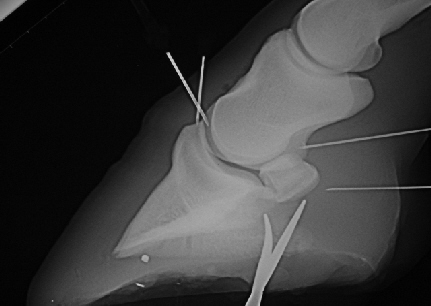

In manchen Fällen ist auch eine Spülung von Gelenk oder Bursa sinnvoll. Besonders wenn von einer Anreicherung von Knorpelabriebprodukten und Entzündungssubstanzen ausgegangen wird, hilft eine Spülung. Eine solche Spülung sollet aus Sicherheitsgründen in Vollnarkose durchgeführt werden, da die Verletzungsgefahr und das hygienische Risiko wesentlich geringer ist. Gelenksinjektionen können hingegen problemlos im Stehen durchgeführt werden sofern die hygienischen Voraussetzungen erfüllt sind.

Spülung von Hufgelenk und Hufrollenschleimbeutel in Narkose. Zwei Kanülen liegen im vorderen Gelenkspalt, eine in der hinteren Aussackung des Hufgelenkes und eine im Hufrollenschleimbeutel.